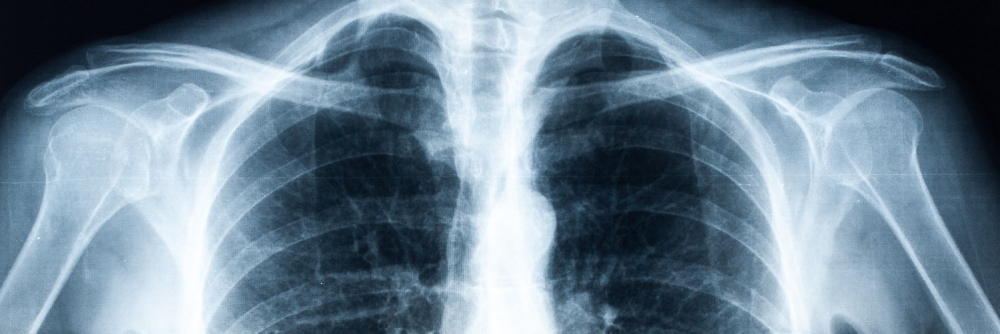

X-ray images help doctors diagnose or monitor a wide range of diseases or injuries.

An x-ray examination is used to produce images of the bones and internal organs. These images and the radiologist’s report can help your doctor diagnose or monitor a wide range of diseases or injuries. Any part of the body can be x-rayed.